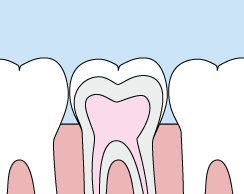

fillingsAt Alta View Dental Care, we provide crowns to improve the shape of your teeth or strengthen a tooth. Crowns are a cosmetic restoration most often used for teeth that are broken, worn, or have portions destroyed by tooth decay.

Crowns or onlays (partial crowns) are needed when there is insufficient tooth strength remaining to hold a filling. Unlike fillings, which apply the restorative material directly into your mouth, a crown is fabricated away from your mouth.

A crown is a "cap" cemented onto an existing tooth that usually covers the portion of your tooth above the gum line. In effect, the crown becomes your tooth’s new outer surface. Crowns can be made of porcelain, metal, or a combination of the two. Porcelain crowns are most often preferred because they mimic the translucency of natural teeth and are very strong.

Your crown is created in a lab from your unique tooth impression, which allows a dental laboratory technician to examine all aspects of your bite and jaw movements. Your crown is then sculpted just for you so that your bite and jaw movements function normally once the crown is placed.